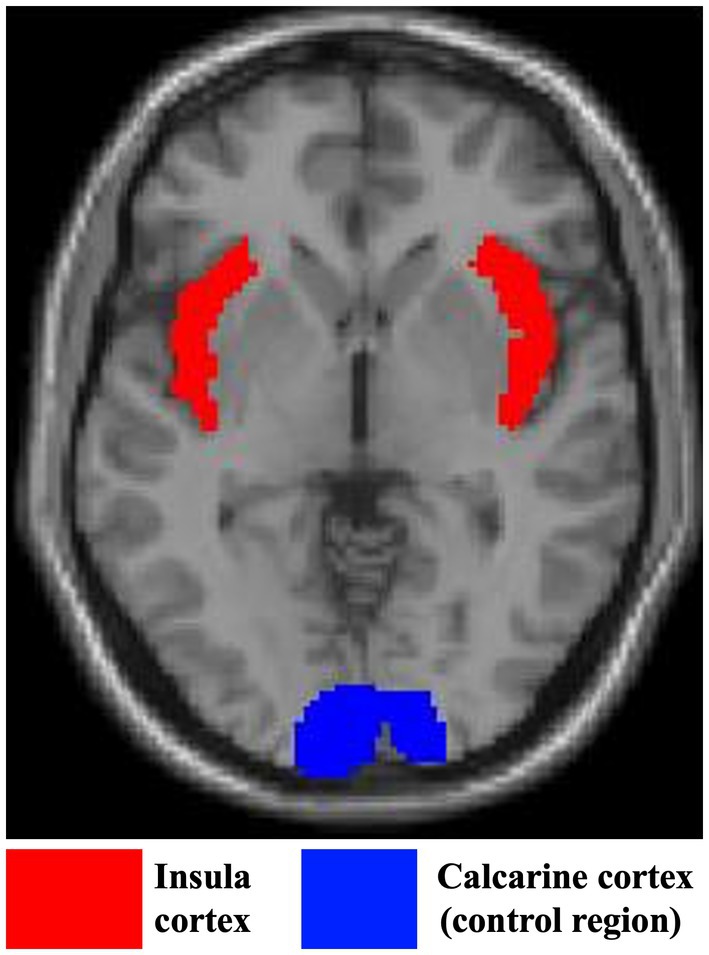

睡眠模式会随着年龄的增长而改变,而内感受——一个涉及身体内部感觉的多层面概念——可能是这些变化的潜在机制之一。脑岛皮层是控制内感受和睡眠的关键区域,可能是一个共享的神经链接。在这项研究中,我们研究了脑岛在将多重内感受性结构与客观测量的睡眠联系起来方面的作用。我们还研究了在不同焦虑水平下,内感受与成人一生中睡眠质量的关系。我们测量了70名年龄在18-79岁的参与者的内感受准确性(检测内部信号的客观能力)、内感受敏感性(检测这些信号的自我感知能力)、岛岛体积(使用结构MRI)、客观评估睡眠质量(通过活动描记术)和特质焦虑。结果表明,这两种内感受性结构都与各年龄段较差的睡眠质量有关,尤其是在焦虑水平较高的个体中。我们还发现,更大的脑岛体积与一个人对内感受能力(内感受敏感性)的更强的主观信念有关。虽然脑岛体积和睡眠质量之间没有直接联系,但脑岛完整性可能通过其与内感受性的关联间接影响睡眠质量。这些发现强调了在整个成人生活中,内感受和睡眠质量之间的负相关关系。使用以正念或内感受为中心的策略进行睡眠干预应谨慎实施,特别是对于焦虑的个体或内感受敏感性较高的个体。进一步的研究应该包括睡眠不良者和有各种健康状况的人,以便更好地了解。

Sleep patterns change with age, and interoception-a multifaceted concept referring to the perception of internal body sensations-may be one of the underlying mechanisms of these changes. The insula cortex, a key region for both interoception and sleep, might be a shared neural link. In this study, we examined the role of the insula in linking multiple interoceptive constructs with objectively measured sleep. We also investigated how interoception relates to sleep quality across the adult lifespan at different levels of anxiety. We measured interoceptive accuracy (the objective ability to detect internal signals), interoceptive sensibility (the self-perceived ability to detect these signals), insular volume (using structural MRI), objectively assessed sleep quality (via actigraphy), and trait anxiety in 70 participants aged 18-79. The results indicated that both interoceptive constructs were associated with poorer sleep quality across age, particularly in individuals with higher anxiety levels. We also found that greater insula volume was associated with a stronger subjective belief in one's interoceptive abilities (interoceptive sensibility). Although there was no direct link between insula volume and sleep quality, insula integrity may indirectly influence sleep quality through its association with interoceptive sensibility. These findings highlight the negative relationship between interoception and sleep quality across the adult lifespan. Sleep interventions using mindfulness- or interoception-focused strategies should be implemented with caution, particularly for anxious individuals or those with heightened interoceptive sensibility. Further research should include poor sleepers and individuals with a wide range of health conditions for better understanding.